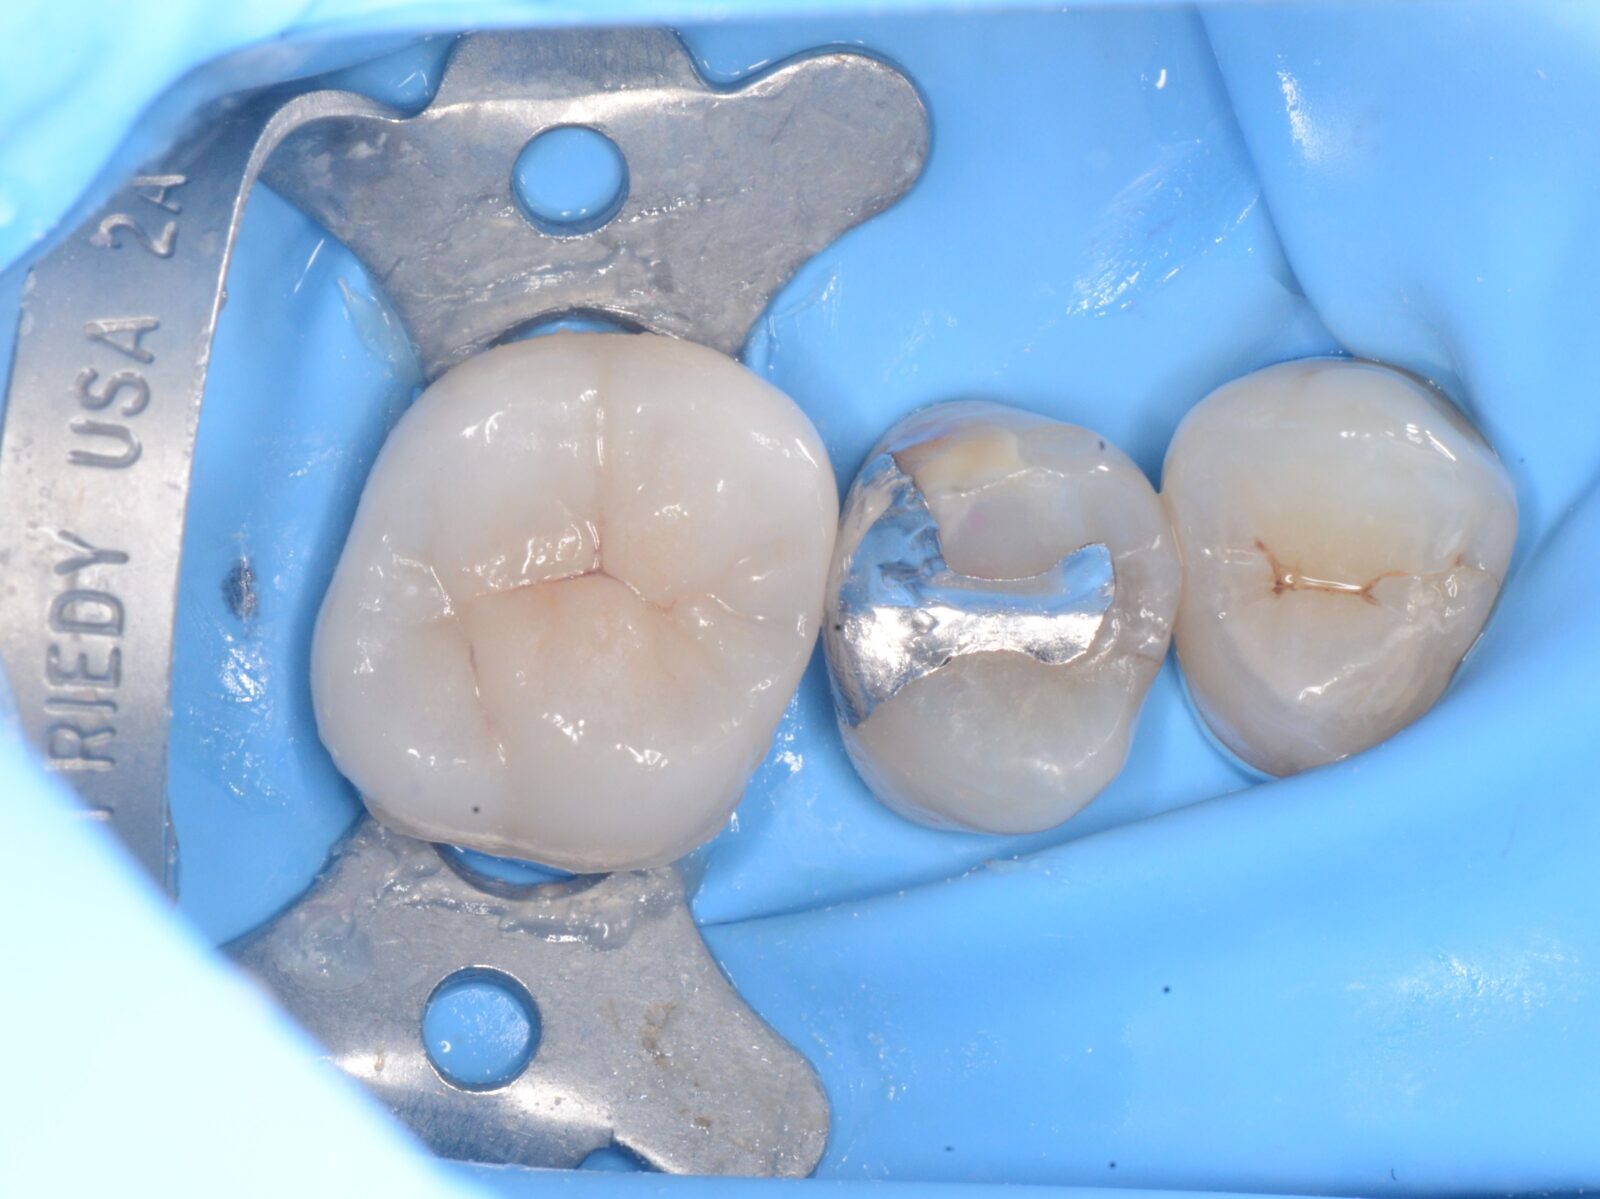

右上大臼歯の銀歯の辺縁から内部にう蝕が進行。

ラバーダム下で完全に除去し、IDS(表面のレジンコーティング)。

その後、完成したセラミックスパーシャルクラウンを通法どおり装着。